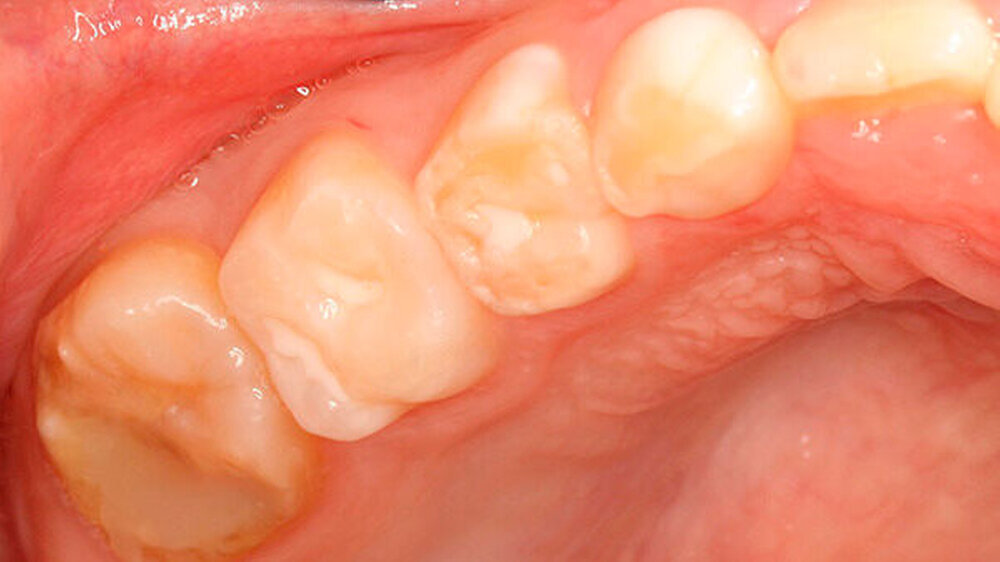

Zu all diesen Faktoren kommt hinzu, dass die nur geringen Erfolge der direkten Füllungstherapie einen häufigen Füllungsaustausch, Reparaturen oder Erweiterungen vorhandener Restaurationen bedingen [Lygidakis et al., 2010] (Abbildungen 3 und 4). Oft schon kommt es noch in der Durchbruchsphase zu ersten posteruptiven Schmelzeinbrüchen [Lygidakis et al., 2010], die meist nur eine temporäre Restauration erlauben.

Die generelle Schwierigkeit in der Versorgung der MIH-Zähne besteht in deren veränderter Zusammensetzung des Schmelzes: Der Anteil organischer Verbindungen ist deutlich erhöht, was neben der Instabilität des Schmelzes (siehe auch posteruptiver Schmelzeinbruch) dazu führt, dass das für die adhäsive Füllungstherapie erforderliche Ätzmuster in der Regel nicht ausgebildet werden kann [Crombie et al., 2013].

Die eingebrochene Zahnhartsubstanz zu entfernen, wobei in der Regel die Kavitätenbegrenzung dann noch in der betroffenen Zahnhartsubstanz liegt und deshalb mit erneuten Einbrüchen jenseits der Restauration zu rechnen ist.